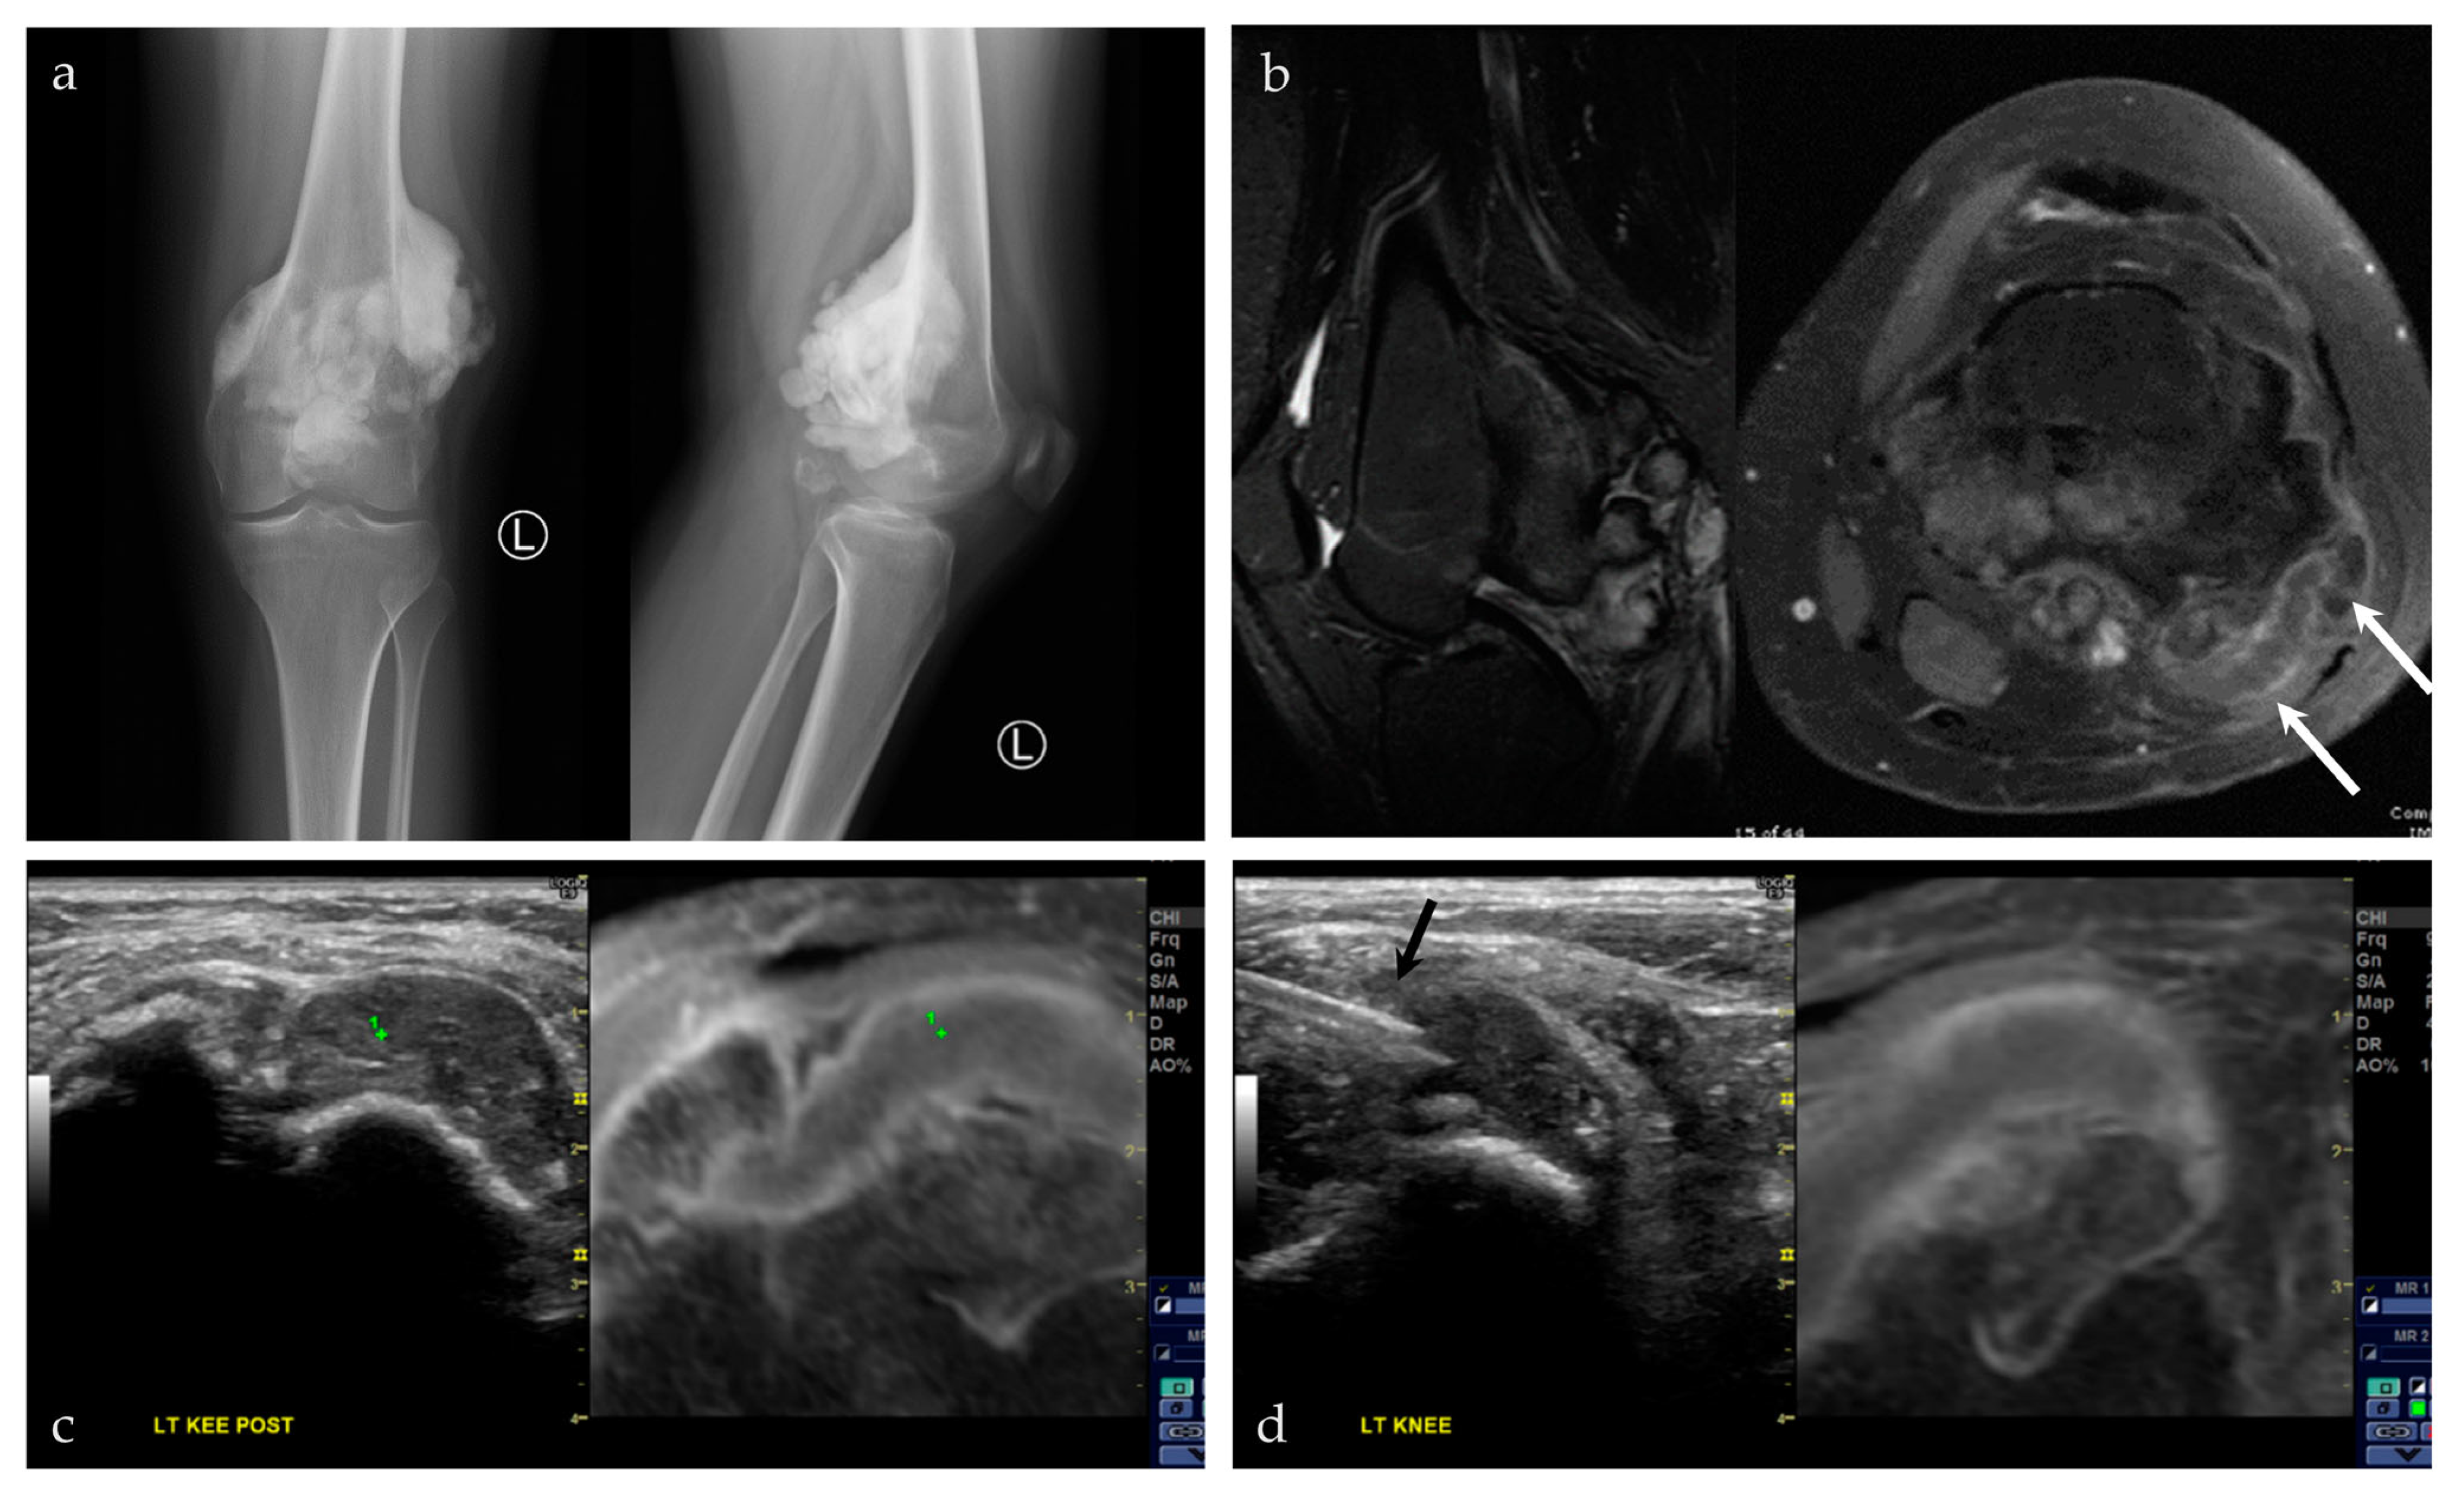

3.2.4. Targeted Percutaneous Lesion Biopsy and/or Aspiration

| 18/F | Left posterior knee | US-MRI | Parosteal osteosarcoma, with a chondroblastic component | Neoplastic, malignant |